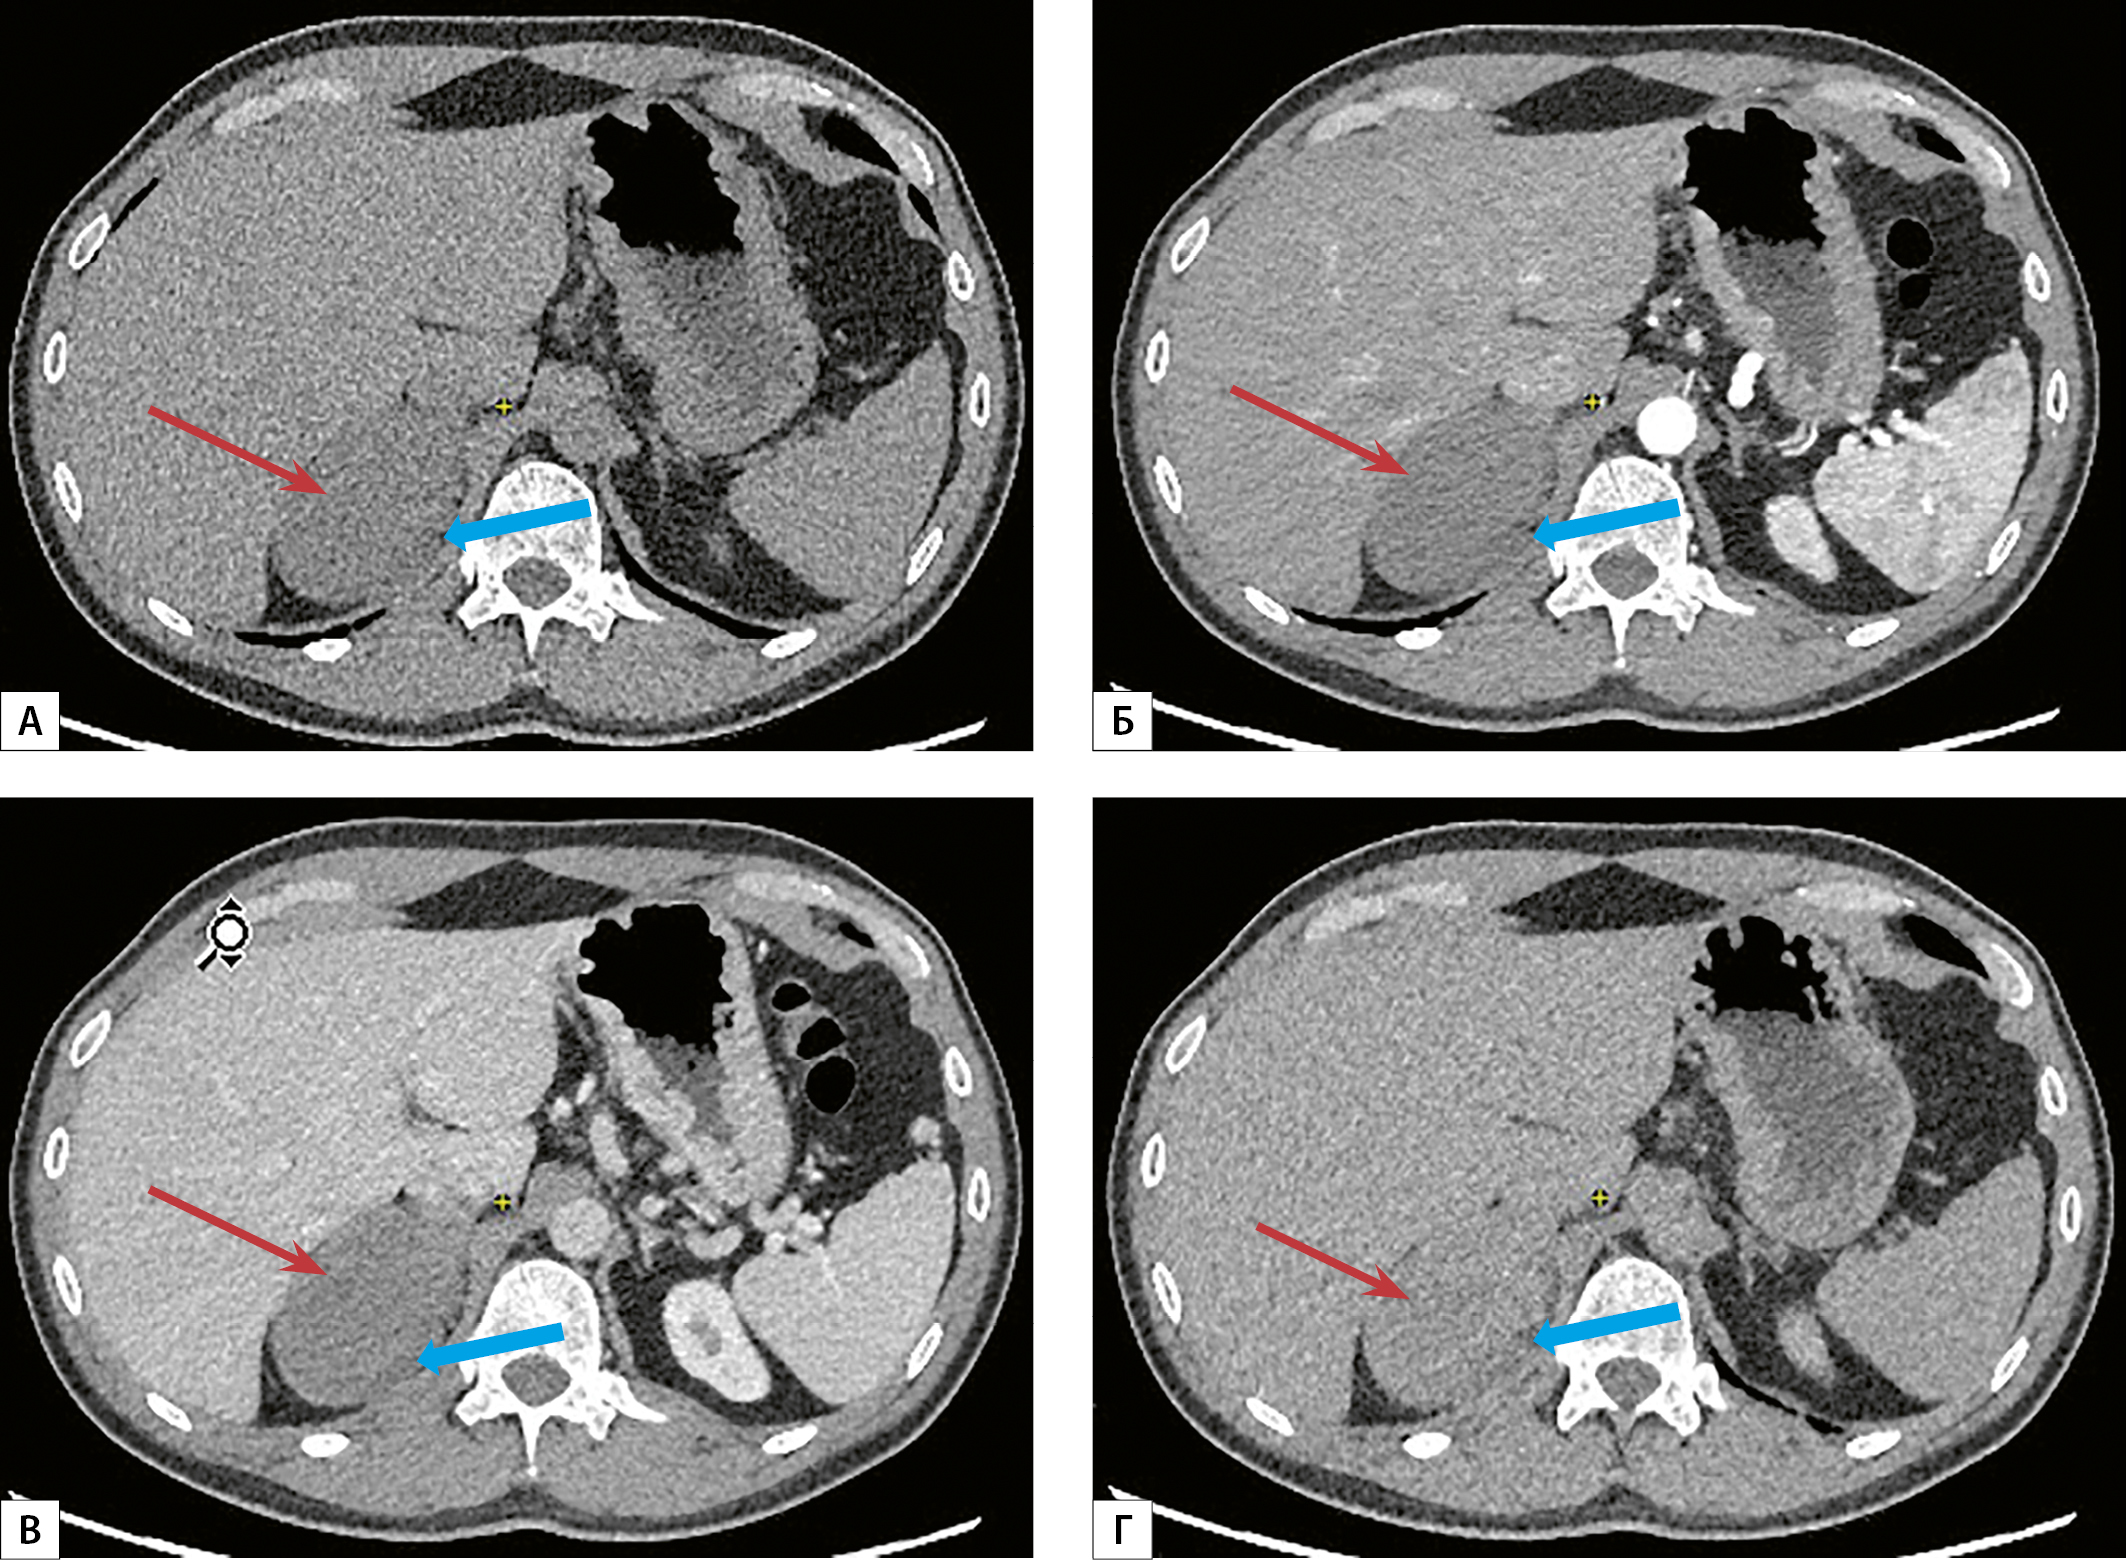

1. Рисунок 1. МСКТ органов брюшной полости с внутривенным болюсным контрастированием: А — нативная фаза, Б — артериальная фаза, В — венозная фаза, Г — отсроченная фаза. Образование правого надпочечника овальной формы с неровными нечеткими контурами (красная стрелка), плотностью по фазам (нативная-артериальная-венозная-отсроченная) 40-45-55-70 ед.Н, по медиальному его контуру определяется вытянутой формы структура, интимно прилежащая к образованию (синяя стрелка). | |